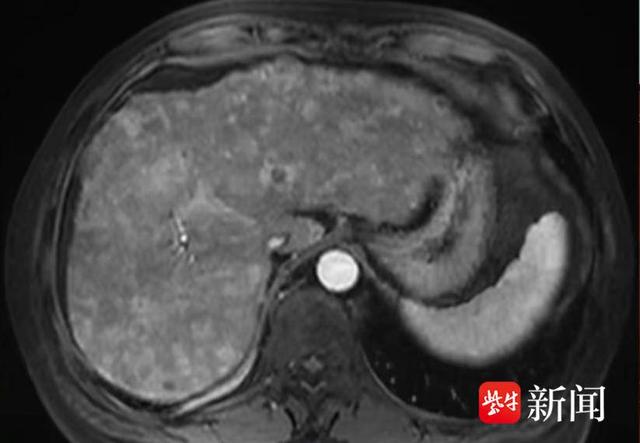

这些肿瘤生长缓慢,无转移能力,通常不会威胁生命恶性肿瘤除原发性肝癌外,其他器官的恶性肿瘤如结直肠癌乳腺癌可能转移至肝脏,形成转移性肿瘤炎症或感染肝炎肝脓肿等疾病可导致肝脏局部炎症反应和组织增生,形成占位性病变其他病变肝囊肿肝包虫病肝硬化等也可能表现为肝脏实质性;肝占位的定义肝占位是在影像学或超声检查时发现肝脏内存在异常占位性病变的统称肝癌的可能性虽然肝占位在临床上有50%的可能性是肝癌,但并不意味着所有肝占位都是肝癌良性病变的可能性有些良性的病变,如血管瘤脂肪瘤以及肝脏内的纤维结节等,也可能出现肝占位性的效应诊断方法为了确诊;占位性病变的性质可能是良性的如肝血管瘤肝囊肿局灶性结节增生,也可能是恶性的如原发性肝癌转移性肝癌因此,肝占位仅提示“肝脏有东西”,需进一步检查明确性质肝癌是明确的恶性疾病肝癌特指发生在肝脏的恶性肿瘤,包括原发性肝癌如肝细胞癌胆管细胞癌和转移性肝癌其他器官肿;定义与影像学表现肝占位指肝脏内异常占位性病变,包括良性如肝囊肿肝血管瘤和恶性如肝癌病变影像学检查超声CTMRI可发现异常病灶肝囊肿表现为边界清晰的无回声区,肝血管瘤呈现高回声且边界规整肝癌在CT平扫中常为低密度灶,增强扫描呈“快进快出”特征动脉期快速强化,门静脉;肝脏占位包括良性疾病和恶性疾病,在临床过程当中,最常见的是肝脏的恶性肿瘤,包括肝癌以及肉瘤肝癌的病理类型,包括肝细胞癌和胆管细胞癌发生原因主要是由于常年饮酒,导致的酒精性肝硬化还有一部分患者是由于慢性病毒性肝炎反复迁延不愈,也会导致肝硬化,继发成肝癌病人化验甲胎蛋白会明显。

肝脏有实质性占位不一定是肝癌肝脏实质性占位的可能病因多样除肝癌外,肝血管瘤肝腺瘤局灶性结节增生肝硬化结节等良性疾病或病变均可表现为实质性占位例如,肝血管瘤是肝脏最常见的良性肿瘤,多无症状,常在体检中发现,通常无需特殊治疗,但需定期复查观察变化肝腺瘤多见于育龄期女性,与;恶性肝占位主要指肝癌,包括原发性肝癌和转移性肝癌原发性肝癌起源于肝细胞或胆管细胞,与肝炎病毒感染肝硬化酗酒等因素密切相关,早期可能无症状,晚期可出现腹痛黄疸消瘦等症状转移性肝癌是其他器官的恶性肿瘤通过血液或淋巴系统转移到肝脏形成的病灶,其治疗需结合原发癌的类型和分期诊断;如果是肝脏的占位有可能是囊性的,也有可能是实性的,囊性的占位包括肝脓肿肝囊肿肝血管瘤等肝实性的占位包括肝的腺瘤肝脏原发现的肝癌以及转移性的肝癌等等通过B超CT或者核磁,可以发现肝脏上有一些占位性的病变,如果不能明确诊断,建议经皮经肝穿刺活检取病理,可以明确诊断;肝实质占位的定义指在肝脏正常结构中出现异常团块或肿物,其性质需通过进一步检查明确可能原因多样肝实质占位的病因涵盖多种类型,包括良性肿瘤如血管瘤腺瘤恶性肿瘤如原发性肝癌转移性肿瘤炎症性病变如肝脓肿囊肿如单纯性肝囊肿以及血管畸形如动静脉畸形等其中,仅;肝占位的定义肝占位是指在正常肝脏的B超均匀回声或CT均匀密度上,肝实质内出现的异常回声区或密度区的病变这种异常表现可能是由多种原因引起的,并不特指某一种疾病肝占位的可能原因恶性肿瘤包括原发性肝癌和转移性肝癌这些是肝脏的恶性病变,需要高度重视和及时治疗良性肿瘤如血管瘤肝。

肝上长东西不一定是肝癌肝脏出现占位性病变是一个宽泛概念,肝癌仅为其中一种可能,多种良性疾病同样可能导致肝脏占位可能导致肝上长东西的非癌性疾病1肝囊肿常见肝脏良性疾病,多为先天性,由肝内小胆管发育异常所致小囊肿通常无症状,多在体检时发现,无需特殊处理,定期复查即可2肝;分期和治疗时机肝癌整体预后较差,但早期诊断和治疗可显著改善预后,晚期预后则不理想需强调的是,肝占位并非等同于肝癌,良性病变占比高患者发现肝占位后应及时就医,通过详细检查明确性质高危人群如乙肝丙肝患者长期酗酒者有肝癌家族史者需定期筛查,以实现早发现早治疗;治疗方法包括外科手术切除射频消融肝移植等多种手段转移性肝癌肝脏是实体瘤常见的转移部位,全身约有三分之一的肿瘤都可出现肝部的转移病程发展相对缓和,症状可以出现乏力厌食发热等非特异性的症状治疗方法包括手术切除射频消融介入栓塞化疗等综上所述,肝占位并不等于肝癌当发现;三诊断方法 影像学检查超声可初步定位占位并观察其形态CT能清晰显示占位的大小位置及密度特征MRI对软组织分辨率高,有助于鉴别良恶性实验室检查甲胎蛋白AFP是肝癌的重要标志物,其水平升高可能提示恶性病变肝活检通过穿刺获取肝组织样本进行病理检查,是确诊肝占位性质的“金标准”。